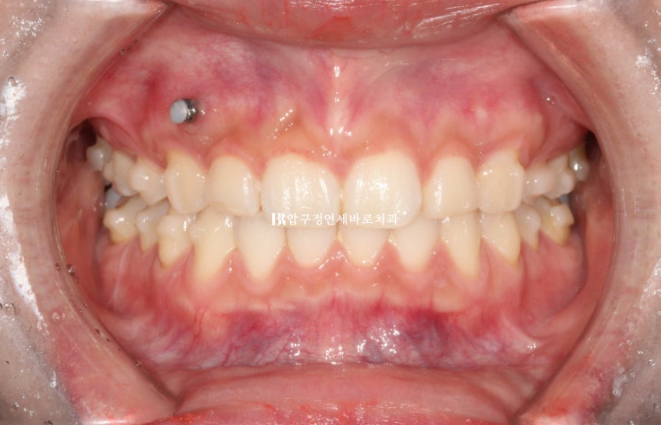

환자분이 고치고 싶은 것은 두가지가 있었습니다.

돌출입과 웃을 때 잇몸이 많이 보이는 거미스마일 이었습니다.

과개교합이 심해서 윗니에 덮여 아래 앞니가 보이지 않습니다.

22.08